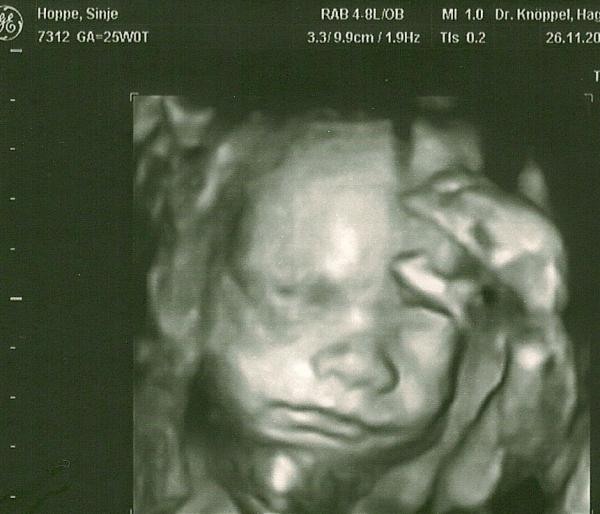

Hallo Ihr Lieben, ich hab langsam echt ein schlechtes gewissen da ich immer nur zum lesen und nicht wirklich zum Schreiben komme :( Naja hoffe dass ich bald mehr Zeit haben werde.. Also heute hatte ich den Zuckerbelastungstest und die Werte waren mega gut .. Dann war ich noch drin und er hat wieder nen langen US gemacht :) Der Kurze ist nun ca 670g schwer und auf den Tag genau entwickelt :) Das freut mich natürlich... Dann hab ich noch ein 4D Bild bekommen und ein normales:) Das häng ich mal ran... Und ich hab mittlerweile insgesamt 7 kilo zgenommen... De Doc meinte das wär ok und nicht bedenkenswert aber ich find es sehr viel und werd mal sehn dass es nicht so schnell weiter geht :) So Ihr Lieben muss auch wieder los.... Drückeuch ganz ganz dolle

Bild zu VU Zuckertest und 4D Bildchen :) - Forum für März - Mamis

Hallo, Patin!! Schön mal wieder was von dir zu lesen. Das ist ja ne kleine süße Maus!! Seh ich das richtig, dass sie ihren Fuss am Kopf hat?? Wie gelenkig die Kleinen doch sind, wahnsinn!! Aber dir gehts soweit gut??